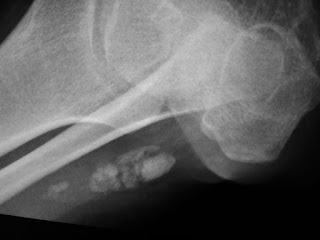

Foot oblique view showing incidental calcification in the achillis tendon